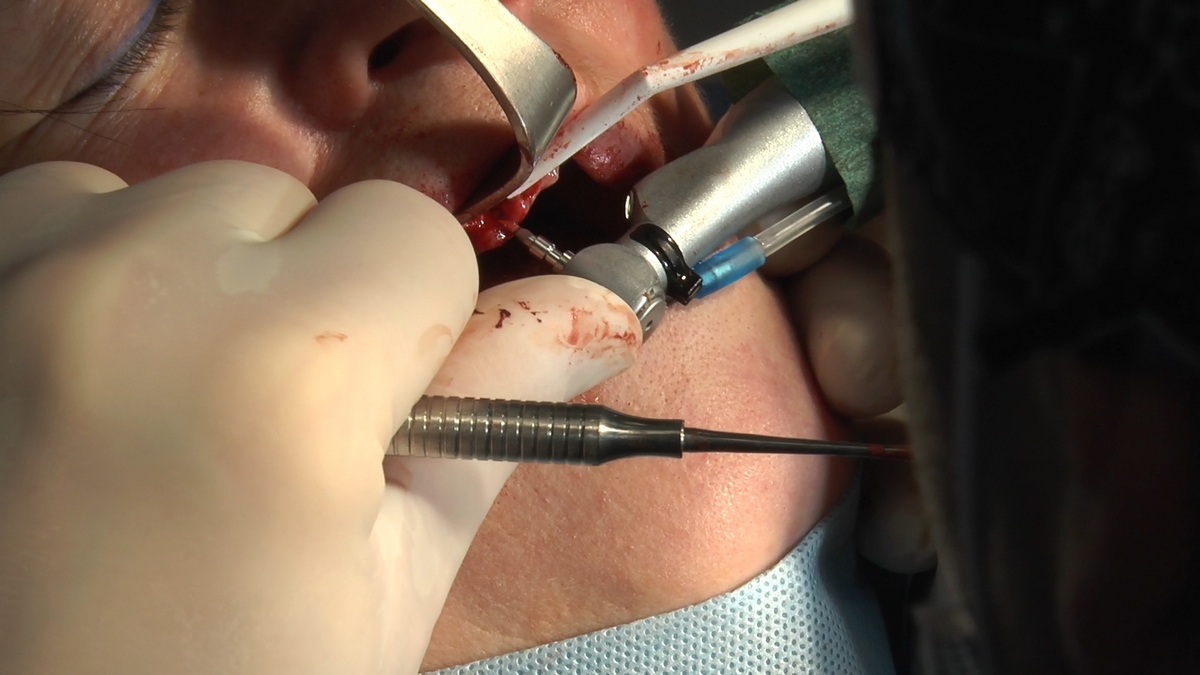

W trakcje dwóch dni zabiegowych, piątek i sobota, 5 i 6 października 2018 roku, lekarze uczestniczący w 6 Sesji VI Sezonu, wykonali wiele zabiegów o wysokim stopniu trudności. Przeprowadzili je pod kierunkiem Mentorów Instytutu Vivadental – dr n.med. Violetty Szycik, dr n.med. Magdaleny Kisłowskiej-Syryczyńskiej oraz dr Małgorzaty Piotrowskiej.

dwa zabiegi All- on -4 / jeden w szczęce, jeden w żuchwie/ z usunięciem zębów i natychmiastową implantacją oraz natychmiastową odbudową protetyczną